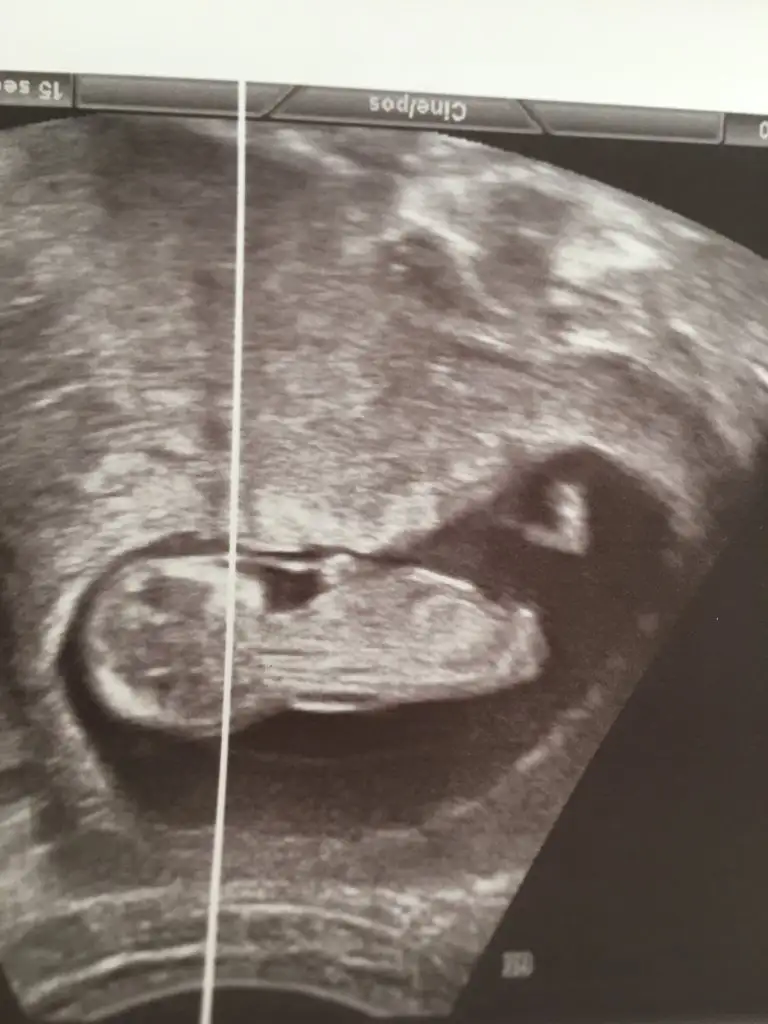

Bunu videodan kestim daha net sanki tahmin edebilcek olan var mı grup çok sessiz 😞😞

• 916A6209-0EAF-4E34-9051-5F3D1402B041.webp

916A6209-0EAF-4E34-9051-5F3D1402B041.webp

27,8 KB · Görüntüleme: 103